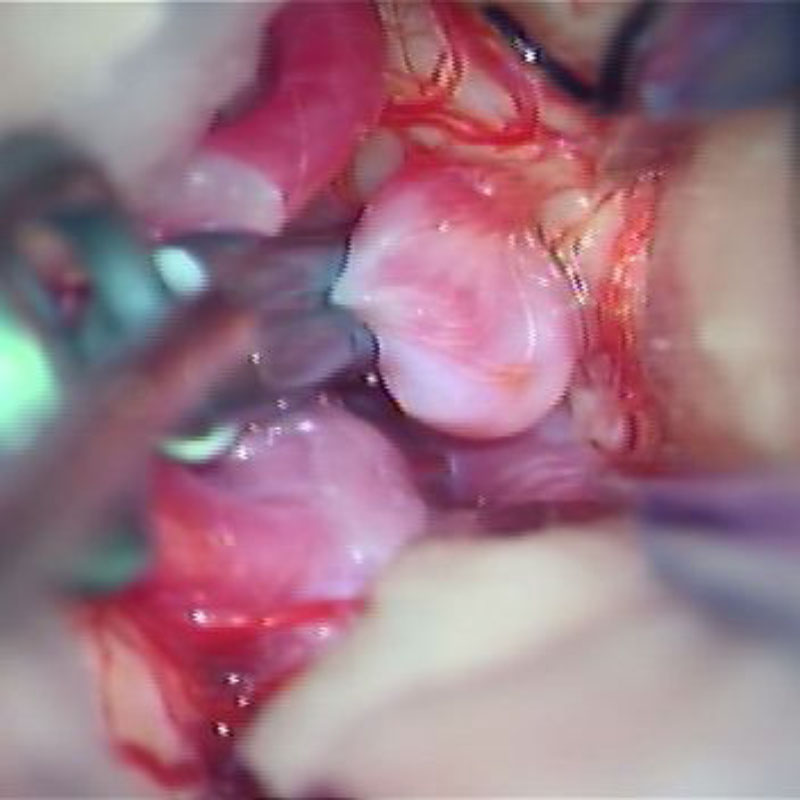

脳底動脈瘤

クリッピング術

手術前

クリップ前

クリップ後